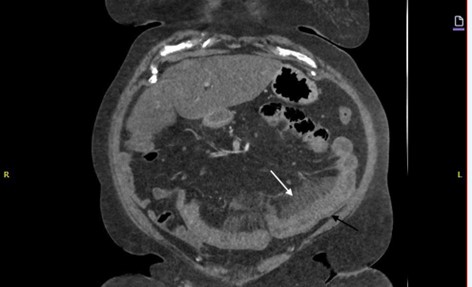

Case Presentation: A 60-year-old Caucasian female with a history of morbid obesity, type 2 diabetes, uncontrolled hypertension, and obstructive sleep apnea presented to the emergency department with chief complaint of a headache. Her blood pressure was elevated, and she was discharged on lisinopril 20 mg daily.Two days later, she returned with severe, diffuse abdominal pain, watery diarrhea, nausea, and vomiting. Her vitals were stable, and the physical exam showed mild abdominal tenderness without guarding or rigidity. A CT scan revealed small bowel thickening, mesenteric stranding, and reactive free fluid (Figure One). Initial lab work showed leukocytosis at 14.93 (normal- 4.5 to 11.0 × 109/L), elevated hemoglobin at 16.0 (normal- 11.6 to 15 grams per deciliter), and increased hematocrit of 48.5 (normal- 36 to 48%). Electrolytes and stool tests were normal, and EKG showed normal sinus rhythm. These findings support the diagnosis of intestinal angioedema, particularly when coupled with the patient’s symptoms (abdominal pain, nausea, diarrhea) and recent initiation of lisinopril. The absence of significant inflammatory markers or other structural abnormalities helps rule out alternative causes, strengthening the case for drug-induced angioedema.